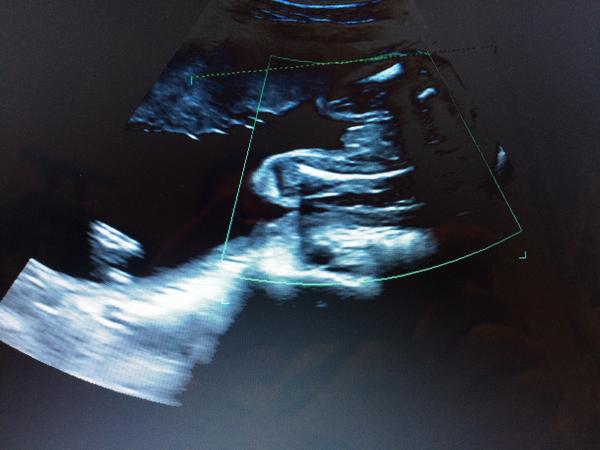

@akinimoddd má dost nohy u sebe,já bych to viděla na pupečník,protože v tomhle týdnu už jsou dost dobře vidět kuličky ;) viz. moje album u druhého i prvního syna kolem 20tt ;)

@snekule mne to tedy prijde jako kluk. Vsak je to vic pred telem,holcicka ve 25tt uz ma krasne videt zrno

@snekule koukni. Sice ty dva utz jsou uplne ciste a jasne viditelne. Ale vic bych se priklanela ke klukovi,kdyz to porovnas s tim svym utz